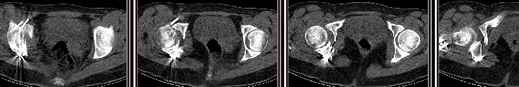

30/11/04 |  30/11/04 |  30/11/04 |  14/12/04 |  14/12/04 |  14/02/05 |  14/02/05 |  21/02/05 | Уважаемые коллеги! Случилось вторичное смещение вертлужной впадины после операции. Посоветуйте, что делать. Пациентка 18 лет. Травма 19.11.04. D.s.: Закрытыый Т-образный высокий перелом правой вертлужной впадины. Закрытый перелом м\мыщелкового возвышения левой б\берцовой кости. 9.12.04 операция - открытая репозиция, остеосинтез переломам вертлужной впадины. 30.12.05 выписаны на амбулаторное лечение с рекомендациями не вставать на правую ногу. 14.02.05 при контрольном осмотре на Р-граммах выявлено вторичное смещение передней колонны. Клинически подвывиха нет, имеется умеренная приводящая контрактура правого тазобедренного сустава, гипотрофия мышц н\конечностей. Госпитализирована в травмотделение. Выполнено КТ. Имеется смещение передней колонны кнутриЮ диастаз 8 мм. Посоветуйте пожалуйста, что предпринять в данной ситуации.

Сустав-то как раз неплох, поскольку впадина почти вся конгруэнтна, по крайней мере вся нагружаемая часть, и подвывиха бедра нет. Артроз в перспективе тут, конечно, не исключить, но на первом плане проблема целости тазового кольца, т.е. нестабильное несращение, о чем А. Рунков писал. На седалищной дефект, и если и разошедшееся основание лонной не срастется, то болезненные проявления могут быть сразу после начала нагрузки, как ее не отсрочивай.